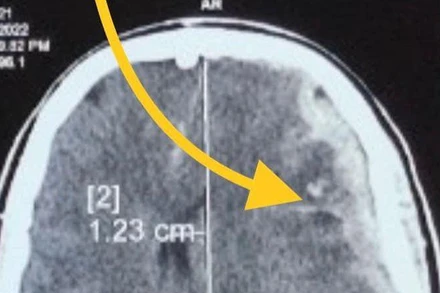

Bệnh nhân cấp cứu tại Bệnh viện Hữu nghị Việt Đức.

Ngày thứ 3 sau bão số 3, Bệnh viện Hữu nghị Việt Đức tiếp nhận 100 ca cấp cứu, trong đó có 50% là ca nặng, đa phần là các trường hợp chấn thương sọ não, kèm theo chấn thương cột sống cổ, ngực, bụng, tứ chi...